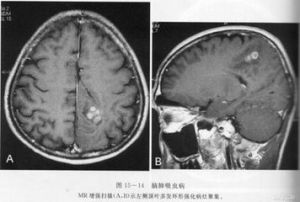

3.頭顱CT掃描和磁共振檢查可見囊腫顱骨片有囊壁鈣化影如合併胸肺型X線檢查可見肺部有明顯改變

②肉芽腫或囊腫期,穴窟病變周圍出現炎症反應,組織壞死液化,其內含夏科一 雷登結晶,周圍為肉芽組織及纖維囊壁形成囊腫、肉芽組織,內有大量蟲卵並可找到成蟲。蟲體有遊走的習性,常從囊 腫內遊走到周圍腦組織,形成新囊腫。諸囊腫間有遂道相通,形成多房性囊腫;

3.腦瘤型除頭痛,噁心,嘔吐等一般顱內壓增高症狀外,尚可有肢體運動障礙及顱 神經損害等定位體徵,可出現視乳頭水腫。腦脊液壓力增高,白細胞及蛋白可輕度增高。此型約相當於蟲體腦內時間較 長,形成較大的多房性囊腫肉芽腫。